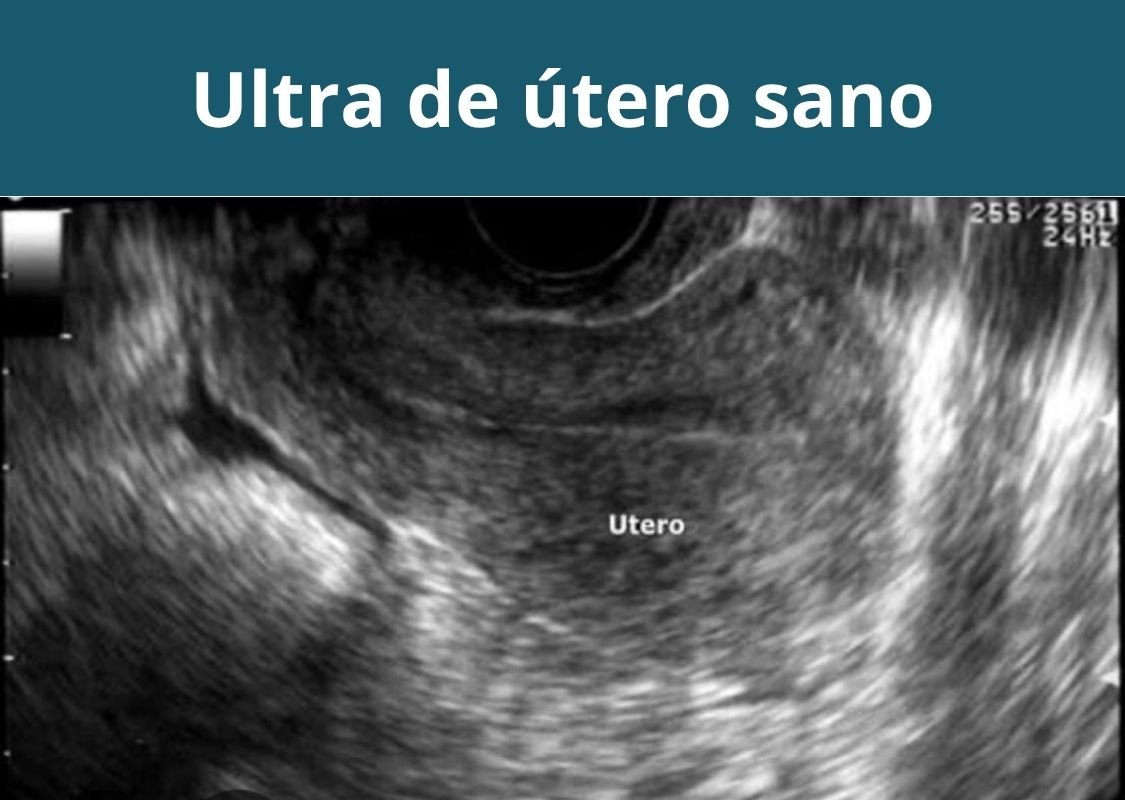

- Ultrasonografía pélvica abdominal (útero y ovarios).

- Ultrasonografía transvaginal (útero y ovarios).

Otras ultrasonografías